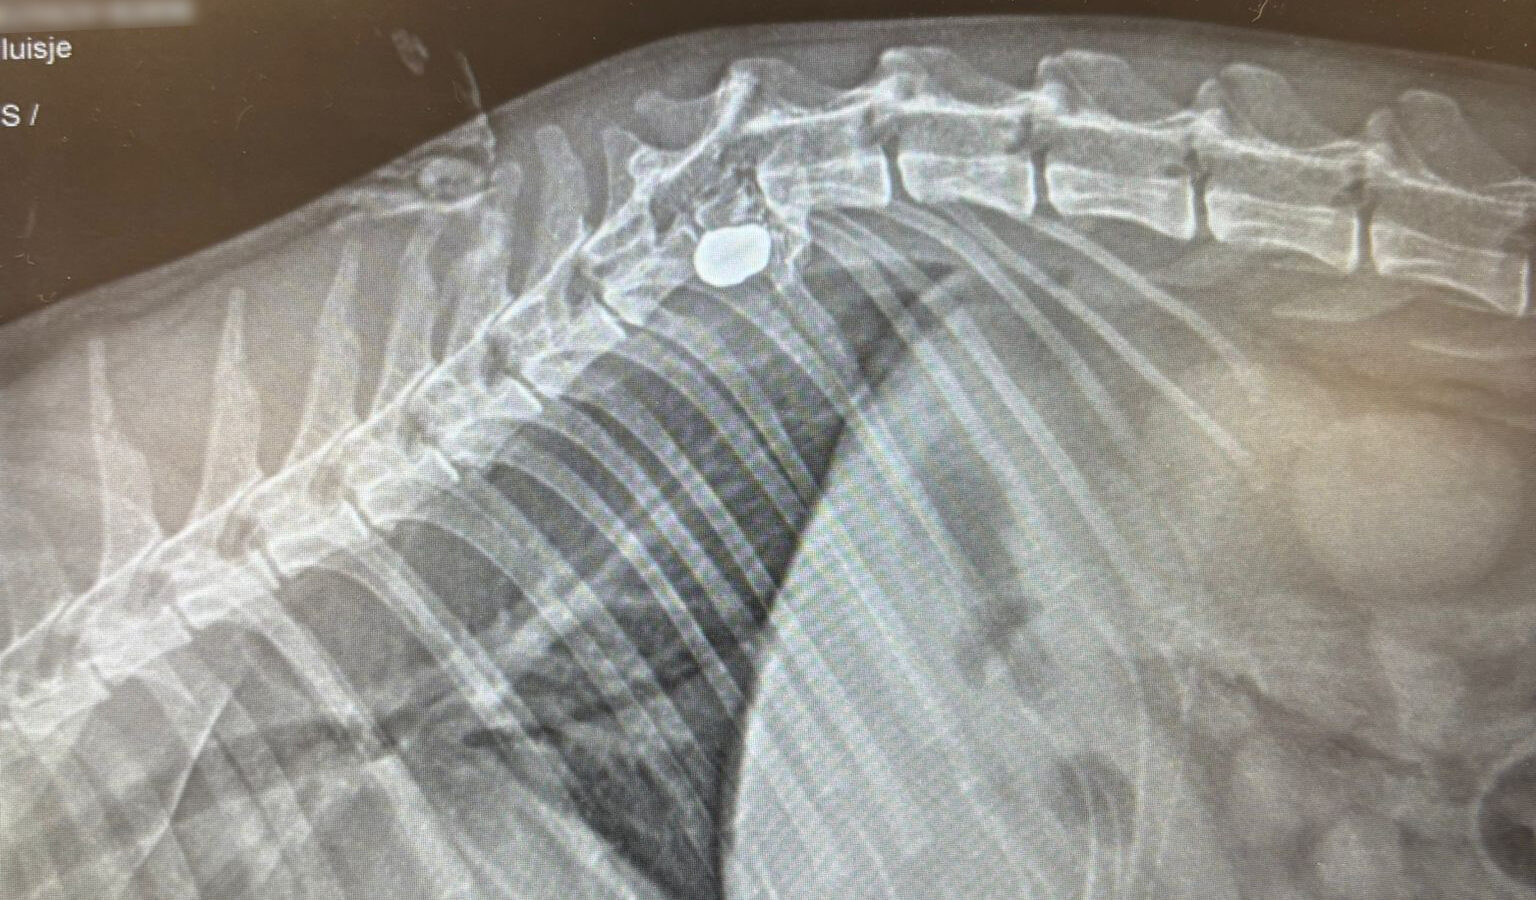

Het kogeltje dat een ruggenwervel van Pluisje heeft geraakt

Met spoed ging het dier naar de dierenarts. Na onderzoek kwam de dierenarts met tranen in haar ogen teruglopen: een kogel had een ruggenwervel geraakt. “Je buik draait twee keer om. Wat is dit nou weer,” zegt Cornee. Er was geen andere keuze dan Pluisje in te laten slapen.